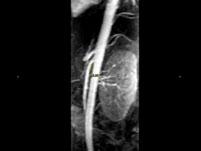

问题 女,24岁,发作性肉眼血尿1年,实验室检查:尿蛋白(-+)、红细胞(12/HP),尿蛋白直立试验(+),CT扫描如图,下列说法正确的是 ( )

选项 A.双肾大小形态正常 B.左肾静脉走行至肠系膜上动脉与腹主动脉间变细,近左肾处扩张 C.左侧肠系膜上动脉与腹主动脉夹角变小 D.左侧肠系膜上动脉与腹主动脉夹角增大 E.考虑为左肾静脉胡桃夹综合征

答案 ABCE